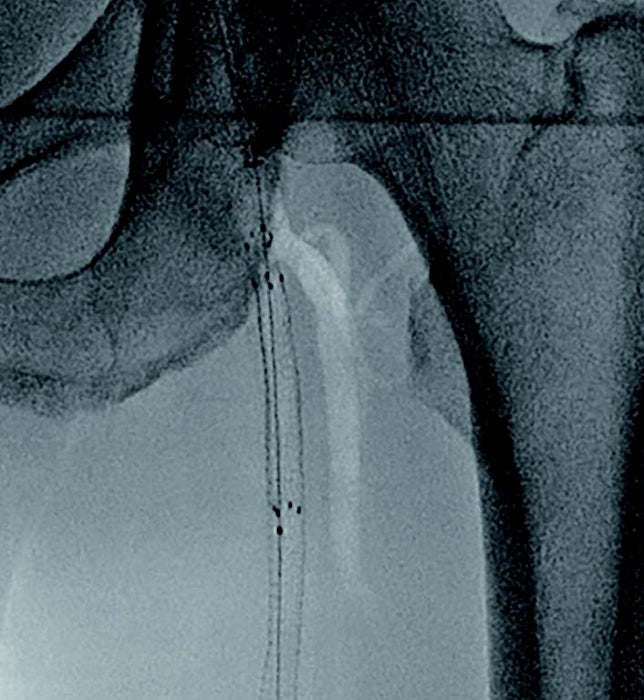

- 対象病変部位(図1): 左 SFA 閉塞(病変長約22 cm)

図1:術前